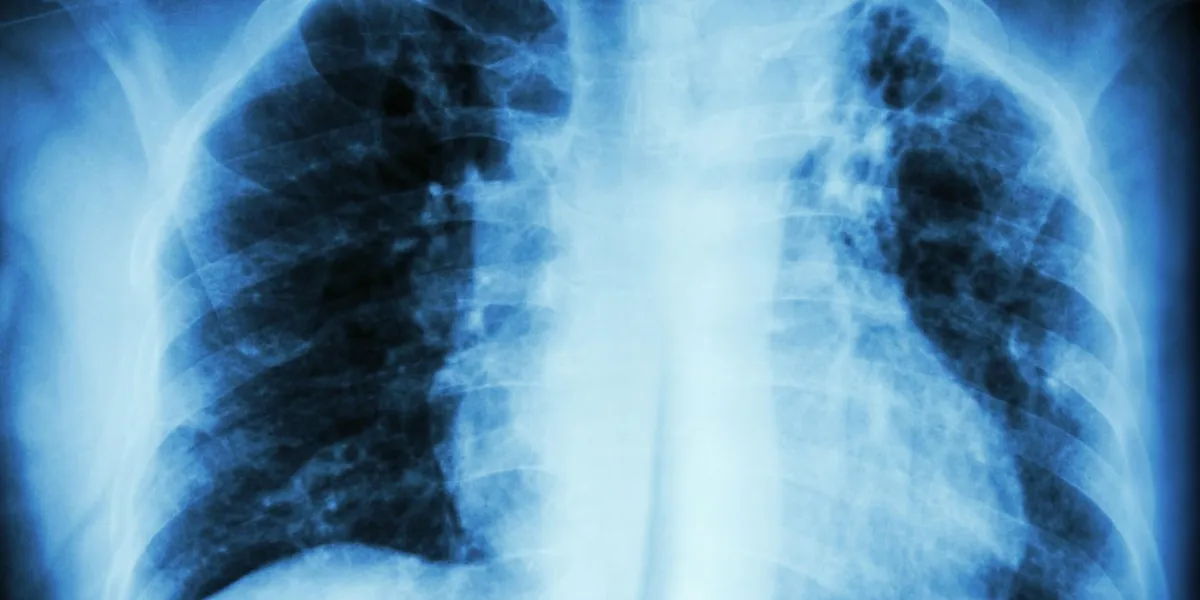

tuberculose pulmonaire infiltration interstitielle aux rayons x du poumon supérieur gauche due à une infection à mycobacterium tuberculosis